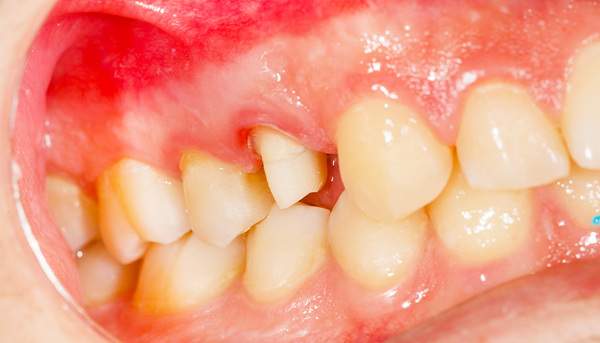

歯石はプラークの溜まり場と先述しました。その歯石をとっていくのですが、歯ぐきの外だけに歯石がついていればいいのですが、中につくこともあります。中についたもので、深い位置にあるものは専用の器具でもなかなかとれませんので、外科的に歯ぐきを切ってから歯石を取り除くこともあります。歯の動揺が強い場合には抜歯になります。